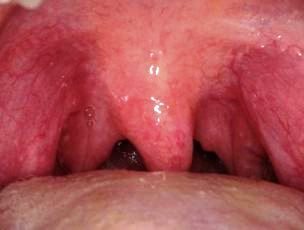

Primary HSV-1 lesions on the uvula and tonsillar pillars.

Photo courtesy of Dr Federico Brugnami